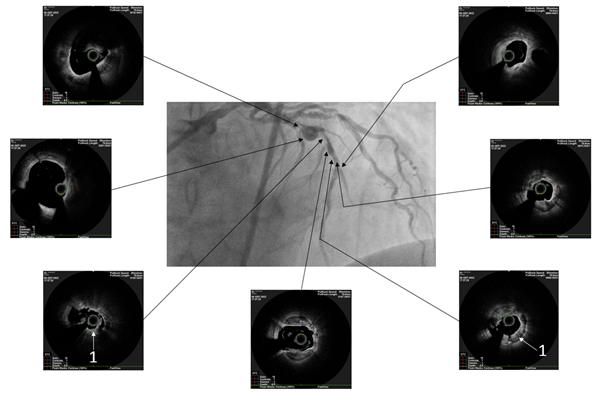

The patient underwent endovascular rotational atherectomy followed by stenting of the affected segments of the coronary arteries. The intervention was carried out under the control of optical coherence tomography (OCT). Initially, the right common femoral artery was punctured under local anesthesia and a 7F introducer was placed. Next, the guide catheter was placed at the mouth of the LCA. The coronarogram revealed 80% calcified stenosis in the terminal LCA OS with a transition to the proximal segment of the LAD and 90% calcified stenosis in the middle segment of the LAD (Figure 1). Using a microcatheter, a conductor was introduced into the apical segment of the LAD. Next, the destruction of calcified atherosclerotic plaques in the LCA and LAD was performed using the Rotablator system of rotational atherectomy (Figure 2), after which, under OCT control (Figure 3), predilatation of the stenotic areas of the LAD with a 2.25x15 mm balloon catheter was performed, followed by positioning and implantation in the area of residual stenoses in the middle segment of the LAD, the proximal segment of the LAD and the OS of the LCA of everolimus drug-eluting stents 3x38 mm and 4x38 mm, respectively. Then, post-dilatation of the stented segments with 3.5x20 mm, 4.5x15 mm balloon catheters and proximal optimization in the LCA OS with a 5x15 mm balloon catheter were performed, achieving a good angiographic result: blood flow in the TIMI-3 arteries. On the control image and OCT control, the stents were fully extended, no signs of dissection were detected, and no residual stenoses were found (Figure 4, 5).

Figure 4 Angiographic result of balloon angioplasty and stenting.

Figure 5 Optical coherence tomography after balloon angioplasty and stenting.

White arrows indicate full adherence of stent cells to the vessel wall (acoustic shadows of stent strata) (1) and stent cells in the area of aneurysmal expansion of the vessel (2).